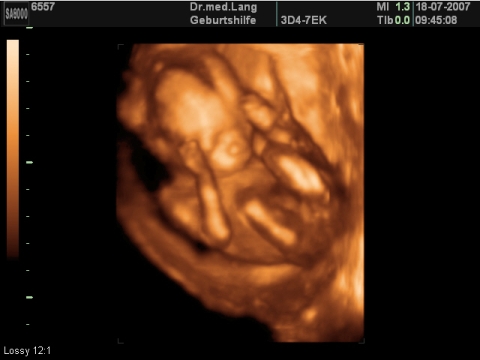

Grösse (Scheitel-Steiss-Länge): 120 mm

Gewicht: 100-150 g

Kopfdurchmesser: 35-44 mm

Die kleine Schilddrüse fängt jetzt mit der Produktion von Schilddrüsenhormon an, was wichtig ist für das weitere Wachstum des Kindes. Sein Fuss misst jetzt 2 cm. Finger- und Zehennägel wachsen, sie sind jedoch noch sehr kurz, sodass es sich bei seinen vielen Turnübungen in Ihrem Bauch nicht kratzen kann. Mit den kleinen Händchen macht es zufällige Entdeckungen. Die Nabelschnur fühlt sich eher ledern an, die Plazenta dagegen ist schön weich.